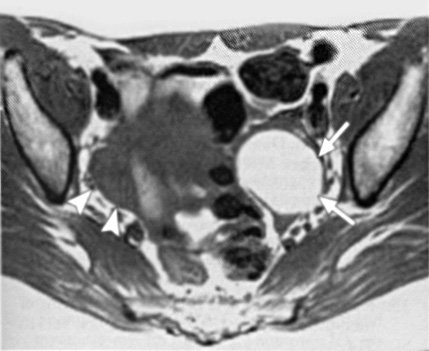

Επιπλέον, στη μαγνητική τομογραφία οι συμφύσεις εμφανίζονται ως χαμηλής έντασης σήματος νηματοειδείς σχηματισμοί, οι οποίοι καθιστούν ασαφείς τις διαχωριστικές επιφάνειες δύο παρακείμενων οργάνων και μπορούν ενίοτε να προσλαμβάνουν σκιαστικό, χωρίς ωστόσο να αυξάνουν την ευαισθησία ή την ειδικότητα της μαγνητικής τομογραφίας. Σύμφωνα με μελέτη των Katayama και συν. εκτιμήθηκε η αξία της μαγνητικής τομογραφίας στην εκτίμηση των πυελικών συμφύσεων χρησιμοποιώντας μια ειδική τεχνική και διαπιστώθηκε πως η ευαισθησία και η ειδικότητα της μεθόδου είναι 72.5% και 87.4% αντίστοιχα. Η οπίσθια κλίση και καθήλωση της μήτρας στον δουγλάσειο, η προσκόλληση των ωοθηκών μεταξύ τους και στην οπίσθια επιφάνεια της μήτρας, η γωνίωση των εντερικών ελίκων, η ανύψωση των οπίσθιων κολπικών θόλων, η εγκυστωμένη συλλογή υγρού και η παρουσία υδροσαλπίγγων αποτελούν έμμεσα ευρήματα, ενδεικτικά συμφύσεων (εικόνα 3).(15,16)

Εικόνα 3. Πυελική ενδομητρίωση με σοβαρές συμφύσεις. Οβελιαία τομή με καταστολή του λίπους στην Τ1 ακολουθία (Α) και κλασική Τ2 οβελιαία τομή (Β), όπου απεικονίζονται πολλαπλές ενδομητριωσικές κύστεις στον δουγλάσειο. Μικρά ενδομητριώματα με υψηλής έντασης σήμα αναγνωρίζονται στην Τ1 ακολουθία με καταστολή του λίπους (βέλη στη τομή Α). Οπίσθια κλίση της μήτρας με ανύψωση του οπισθίου κολπικού θόλου (κεφαλή βέλους στη τομή Β), ενδεικτικά παρουσίας σοβαρών συμφύσεων στον δουγλάσειο. Επιπλέον διαπιστώνεται αδενομύωση στον ορογόνο της οπισθίας επιφάνειας του μυομητρίου (βέλη στην τομή Β).